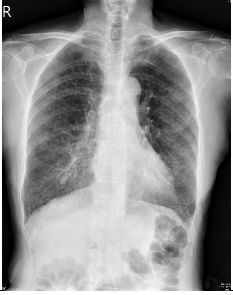

1. A 39-year-old man had this chest X-ray on his health exam. No any clinical symptoms.